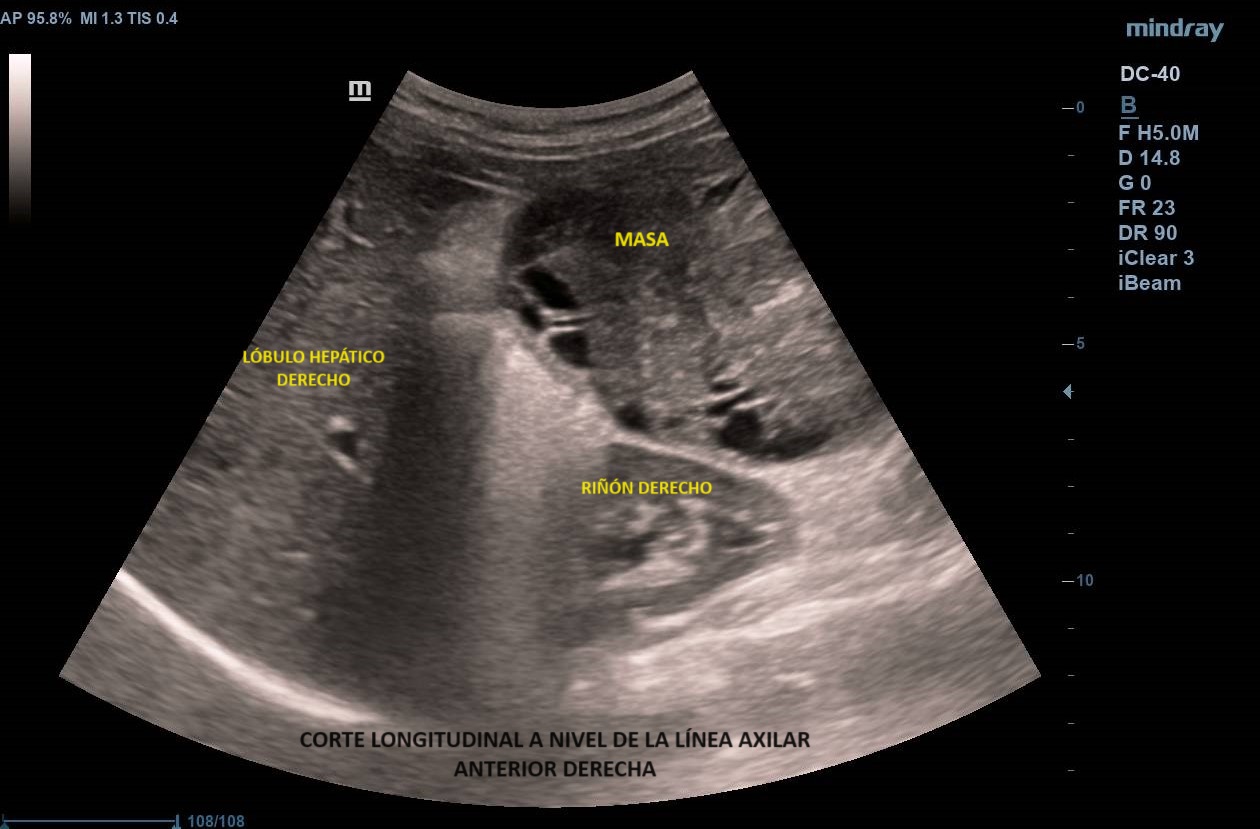

Ecografía abdominal clínica: Masa heterogénea que ocupa todo el abdomen, de aspecto sólido, vascularizada con zonas hipoecoicas-anecoicas en su interior. Riñones con eco-estructura sin alteraciones, hígado sin LOES. Vejiga sin engrosamiento de paredes, útero parcialmente visible. Anejos y retroperitoneo no valorables. No líquido libre.

Se deriva a urgencias donde realizan ecografía transvaginal confirmando presencia de masa que parece depender de anejo derecho. Solicitan TAC toraco-abdomino-pélvico objetivando «masa abdominal gigante de dudosa dependencia ovárica, no pudiendo descartar liposarcoma abdominal». Citan a la paciente para RM donde se demuestra contacto pero no dependencia de masa abdominal, probable liposarcoma, de anejo derecho, de características normales. Analítica con marcadores tumorales sin alteraciones.